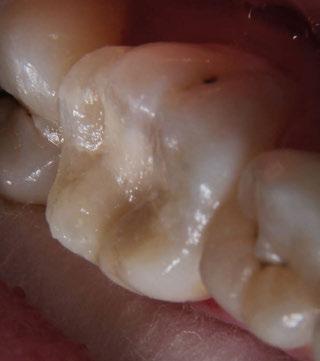

Domenzain-Sanchez y cols. realizaron un estudio transversal de casos y controles con pacientes de 5 a 12 años. Un 80% de los asmáticos presentaban caries, a pesar de que los autores no encontraban relación directa entre caries y enfermedad asmática. Éstos consideran que la medicación es la causa principal de las caries, ya que gran parte se queda en la orofaringe, además de reducir el flujo salival y tener azú cares. Los niños asmáticos tienen 1,02 mayor riesgo de erosión dental que los niños no asmáticos; esto se debe a la acidez de los fármacos que reducen el pH y provocan reflujo gastroesofágico. La mayoría de los estudios no avalan una asociación directa con el bruxismo, ya que en niños es muy frecuente, pero concretamente

en este estudio resultó que un 14% presentaban bruxismo dentro del grupo de asmáticos y lo justifican con la obstrucción parcial prolongada o completa de las vías respiratorias (53).

Gorji y cols. realizaron un metaanálisis para establecer la asociación entre caries y asma. Llegaron a la conclusión de que el asma es un factor de riesgo de caries y de no tratarse adecuadamente y tener las medidas preventivas necesarias, aumenta la probabilidad de desarrollar caries. Atendiendo a la falta de suministro de oxígeno, los ameloblastos se ven afectados y se altera la formación del esmalte, lo que origina defectos sin posibilidad de reparación como el MIH o síndrome de hipomineralización incisivo-molar (9).